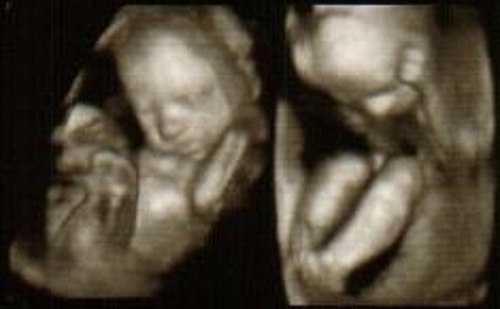

3d/4d УЗИ

Фото УЗИ плода на 24 неделе беременности

При УЗИ плода в 24 недели беременности вес ребенка составляет около 680г., рост – приблизительно 22см. Этот вес и размер обусловлены накоплением жира, интенсивным развитием костной, мышечной ткани, всех внутренних органов.

Все структуры лица уже полностью развиты, глаза имеют ресницы, веки способны открываться и закрываться, брови умеют хмуриться и удивляться. Все структуры лица особенно хорошо можно увидеть и оценить с помощью 3d-4d УЗИ при беременности. При УЗИ плода в 24 недели беременности лицо полностью сформировано, вы можете видеть, на кого похож ваш малыш!

Фетометрия (размеры плода) при УЗИ плода в 24 недели беременности в норме:

- БПР (бипариетальный размер). При УЗИ плода в 24 недели беременности бипариетальный размер составляет 55-67мм.

- ЛЗ (лобно-затылочный размер). При УЗИ плода в 24 недели беременности 71-85мм.

- ОГ (окружность головки плода). При УЗИ плода в 24 недели беременности окружность головки соответствует 201-237 мм.

- ОЖ (окружность живота плода) — при УЗИ плода в 24 недели беременности составляет 102 мм 172 -224 мм.

Нормальные размеры длинных костей при УЗИ плода в 24 недели беременности:

- Бедренная кость 40-48 мм

- Кости предплечья 31-39 мм

- Кости голени 36-44 мм.